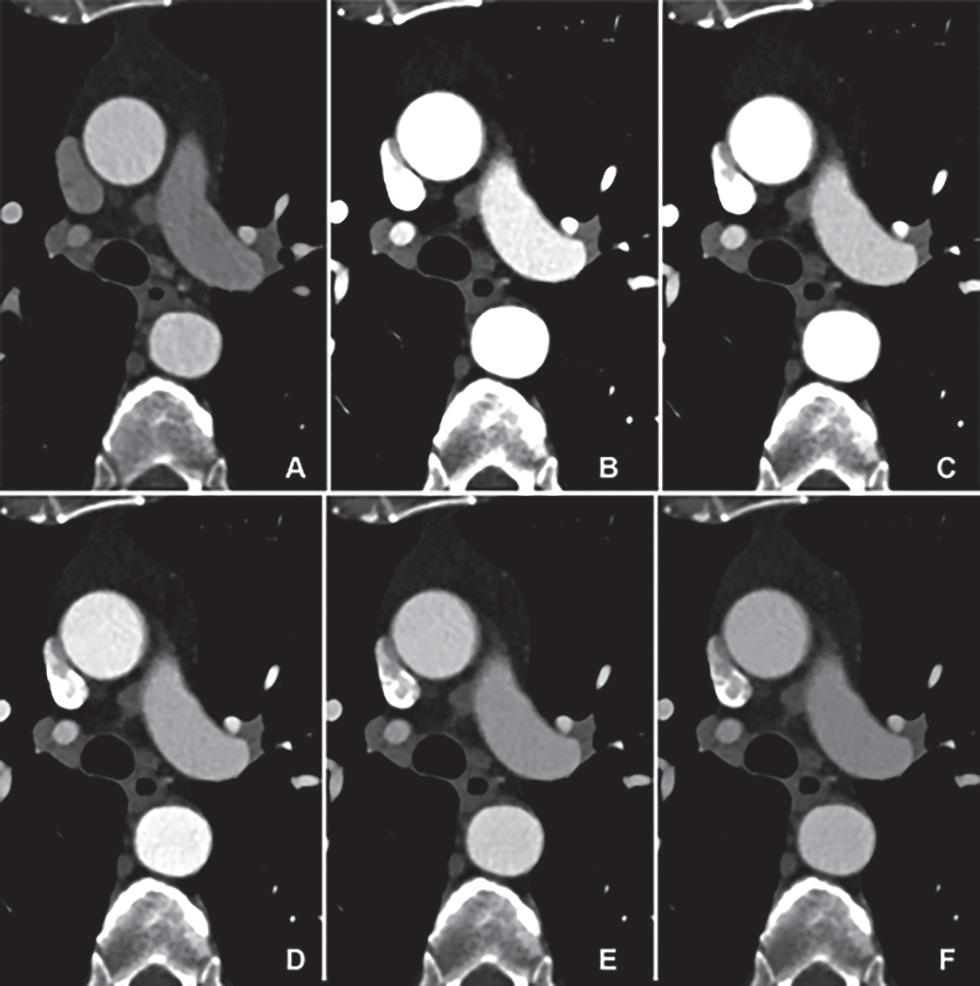

EID CT y PCD CT utilizando un protocolo de medio de contraste idéntico y una dosis de radiación equivalente. Las imágenes transversales de CTA muestran la aorta torácica al nivel del tronco pulmonar en un hombre de 62 años en el grupo 1, que se muestra utilizando configuraciones de ventana idénticas (centro de ventana: 350 HU, ancho de ventana: 1000 HU). (A) Imágenes de exploraciones realizadas con un sistema CT de fuente dual de tercera generación con EID. (B–F) Imágenes de PCD CT con VMI a niveles de energía de 40 a 60 keV. El intervalo de tiempo entre las exploraciones fue de 11 meses. Ambos escaneos se realizaron con el mismo protocolo de medios de contraste (volumen, 70 ml). Tenga en cuenta la mayor atenuación del vaso a niveles de energía más bajos para PCD CT. CTA = angiografía por TC, EID = detector de integración de energía, PCD = detector de conteo de fotones, VMI = imágenes monoenergéticas virtuales.

Figura 5. Comparación de la calidad de imagen entre EID CT con protocolo de medios de contraste estándar y PCD CT con protocolo de medios de contraste de bajo volumen utilizando una dosis de radiación equivalente. Se muestran imágenes renderizadas cinemáticas transversales y tridimensionales de la ATC toracoabdominal en una mujer de 71 años del grupo 2. (A–C) Imágenes de EID CT de tercera generación con selección automática de voltaje de tubo de 90 kVp. (D-F) Imágenes de PCD CT con volumen de medio de contraste reducido de 52,5 ml y VMI a 50 keV. El intervalo de tiempo entre las exploraciones fue de 6 meses. CTA = angiografía por TC, EID = detector de integración de energía, PCD = detector de conteo de fotones, VMI = imágenes monoenergéticas virtuales.